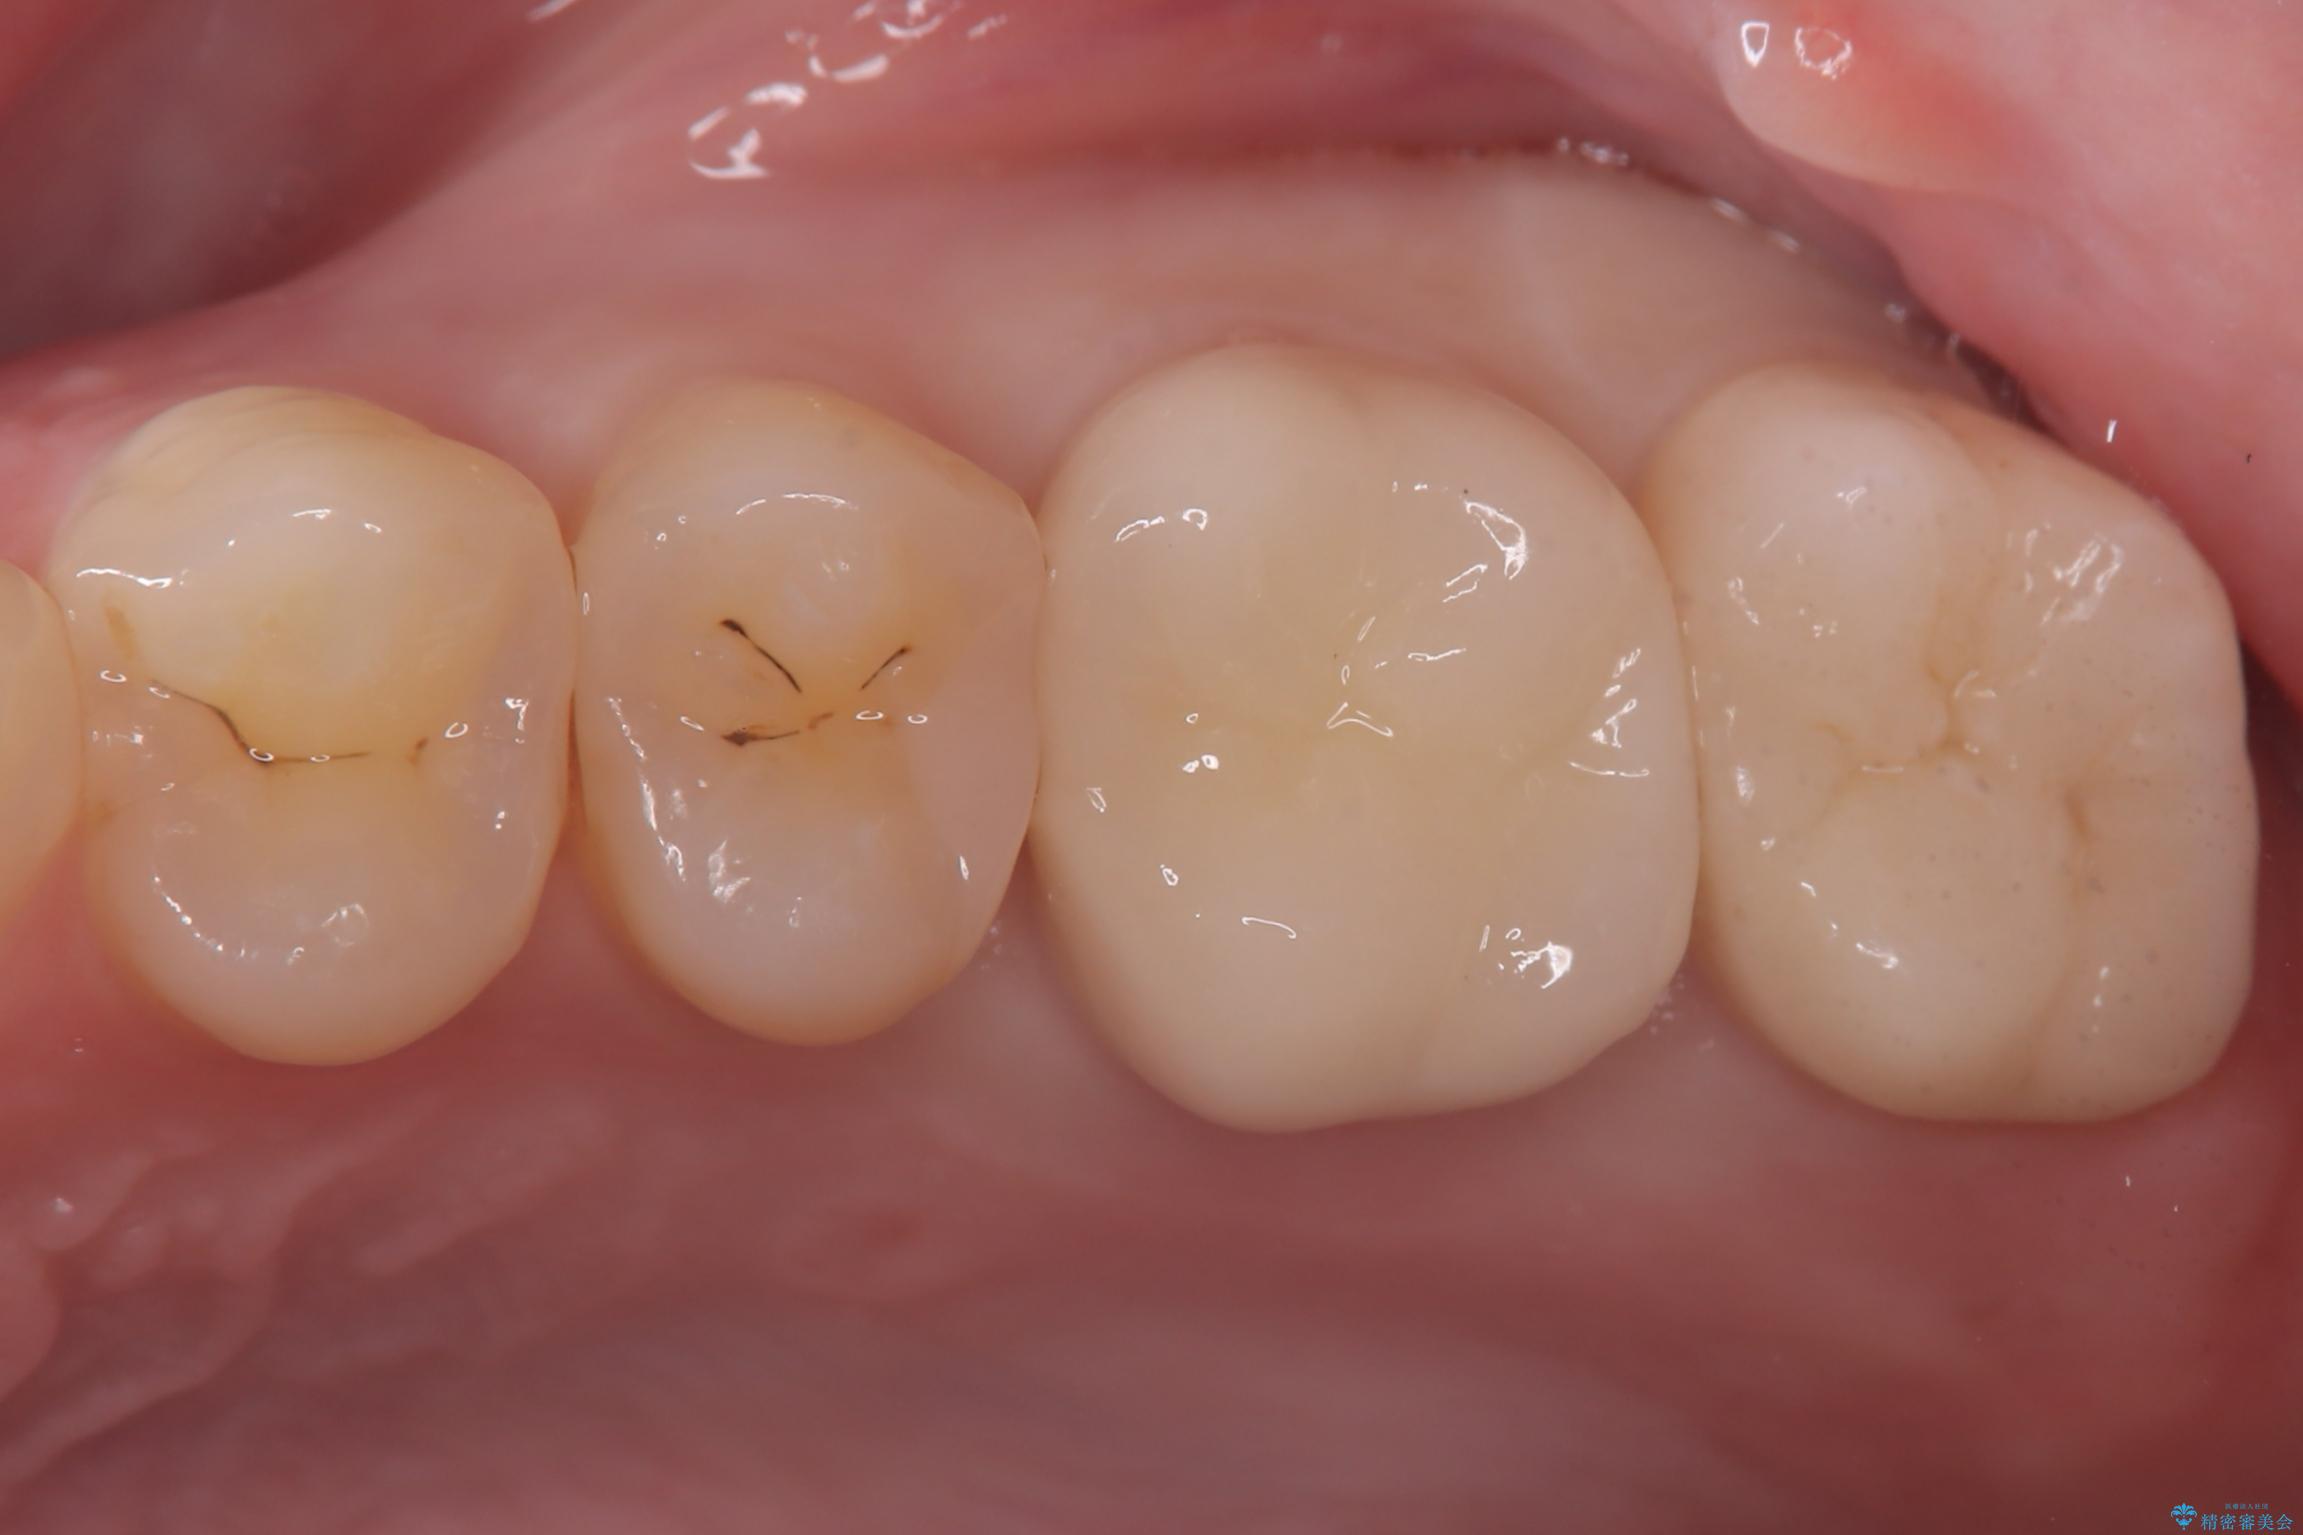

セラミックによる修復: 最終的な被せ物(または詰め物)にはセラミックを使用しました。高い適合性により、二次的な虫歯のリスクを抑えつつ、天然歯のような自然な咬み心地と美しさを再現しました。

経過観察と土台作り: 一定期間の経過を観察し、痛みや炎症がないことを確認。神経の生存を確認した上で、セラミックを支えるための土台を精密に構築しました。